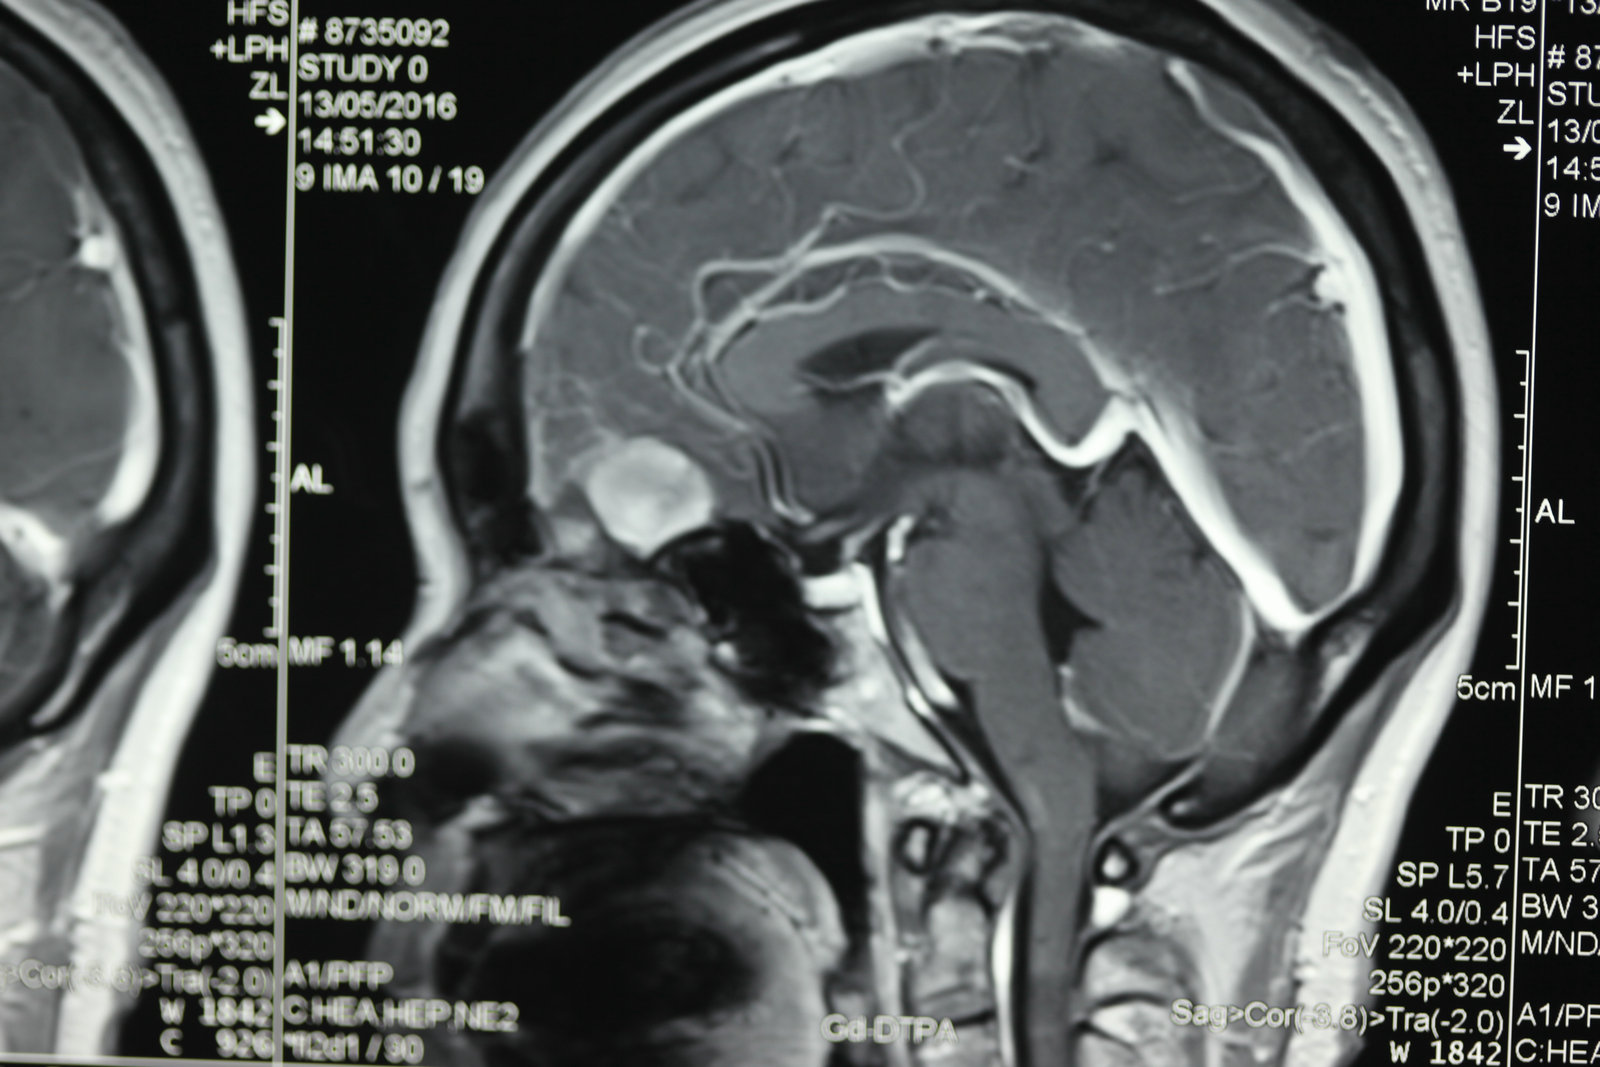

显微神经外科学是以应用手术显微镜为标志,但是,我们决不能片面的将显微神经外科学理解为只要手术中使用手术显微镜就是显微神经外科手术。而显微神经外科学的正确概念,足指以近代影像学为诊断基础,一整套与显微手术相匹配的手术设备、显微神经外科手术器械为保证的,以颅内病灶为中心的手术。显微神经外科学不仅是技术,更重要的是概念的更新。

1.以病灶性为中心手术,减少脑组织损伤:显微神经外科手术将经典神经外科“脑叶范围手术”,推向“病灶性手术”水平,尽量减少干扰脑组织,探索出新的手术入路。譬如,翼点入路、经岩骨入路以及额眶颧入路,这些具有代表性显微手术入路的共同特点是,牺牲部分颅底骨结构获得手术空间,经过脑外抵达病灶,尽量减少对脑的牵拉和损伤。20世纪70年代,Yasargil提出利用颅内自然的解剖间隙和经脑外到达病灶部位,处理病变,降低手术创伤,成为了显微神经外科手术的基本概念。随着对脑功能认识的逐步深入,手术中还对各种神经和脑血流进行监测,加大了对脑和神经的功能保护。

将手术显微镜和显微神经解剖结合,会使许多常规的神经外科手术得到进一步完善,如脊髓的切除、动脉瘤的夹闭等,并开创了以往神经外科医生不能施行的手术。由于对显微神经解剖认识的深入,医生能够以较小的脑牵开或皮层结构切开,经过神经血管间隙,安全准确地达到脑深部病灶,进行微损伤的手术切除。总之,显微神经解剖和显微外科技术结合,可在微创下切除以往不能手术切除的病变。而应用手术显微镜进行神经外科解剖研究和神经外科教学是对以往的肉眼神经解剖研究的全新修正,它使肉眼观测困难的微小结构和纤细神经清晰可辨,属于全新的领域。 手术显微镜的应用又使医生感到手术操作在灵活性和精确性方面受限,因此又有学者开始探索机器人辅助手术,这将开创精细外科技术的新境界,当然它也要求有新的显微解剖知识与其适应。其他新技术的发展也需要以精确的显微神经解剖知识为基础,如在血管内栓塞治疗动脉瘤时,需要详尽了解载瘤动脉、穿通动脉及其解剖变异经过缜密的开颅设计,可达到颅底任何部位。将显微神经外科解剖研究结合影像学定位,利用脑表面的沟裂建立细小孔道,一些脑深部解剖能理想的显露。显微解剖研究也研究了一些新的手术入路,如经脉络膜入第三脑室手术入路、经鼻腔入蝶窦的垂体瘤手术入路等。在未来,通过更深入的显微外科解剖学研究,还会有一些新的更好的手术入路研究出来。另外一些新的手术技术的改进和完善也需要对显微外科解剖的深入理解。 随着神经精细结构显露技术的显著提高,显微解剖照片准确鲜明,生动活泼,非常优美,适合于神经外科学习和参考。